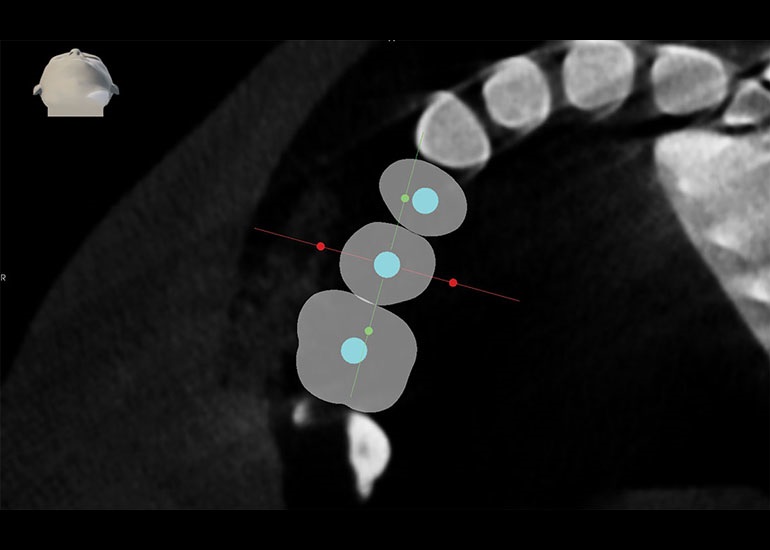

The robot has two arms, a tracking arm (Fig. 2) that attaches to the splint (Fig. 3) and a second arm that holds the implant drill. Once the patient is physically attached through the splint, the robot can “see the patient” in real time because the preoperative markers in the X-ray can now orient between the patient and the robot (Fig. 4). The technology is impressive. If the patient moves during surgery, the robot moves with him or her.

Precision is the operative word here; I had never been able to achieve this level of three-dimensional precision in preplanning and placing dental implants. Location, depth and angulation are all controlled by the robot down to a fraction of a millimeter. The 3D planning software allows me to confidently avoid anatomical features such as nerves and sinus, enabling me to place the implant in the best restorative position.

Recently, I placed three implants in Teeth 3, 4 and 5 in conjunction with a sinus lift. Implants in such close proximity to one another can be a challenge even for a specialist. By using the preplanning software, I virtually placed the implants precisely where I wanted them to go, as shown in Figs. 7, 8 and 9. I was thrilled with the outcome. As you can see on the X-ray in Fig. 10, the implants were placed precisely according to the plan.

Fig. 9: 3D plan shows axial view.